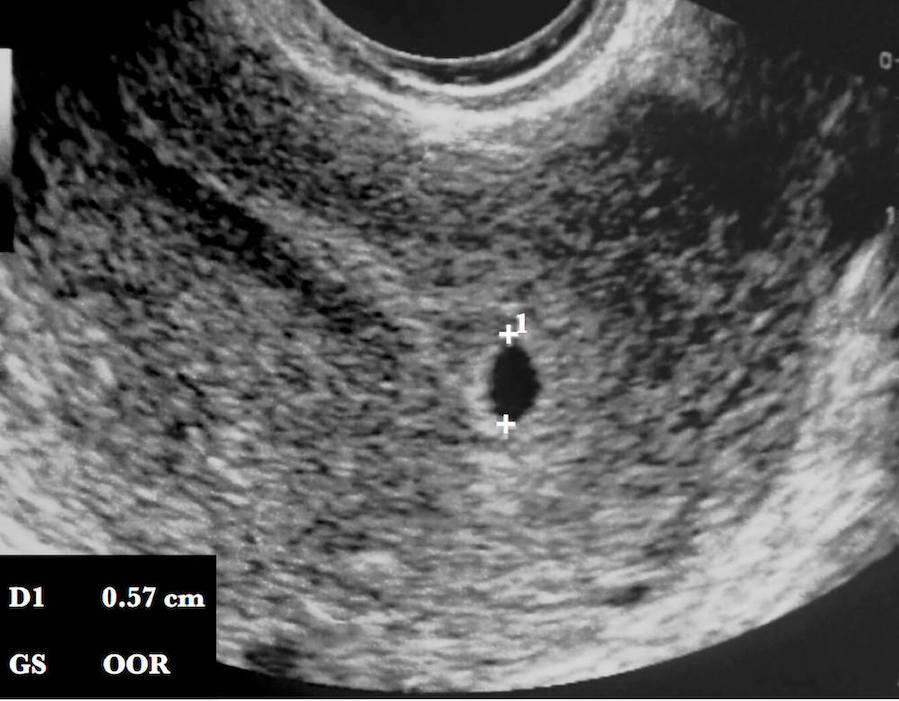

Follows a twin pregnancy in the First Trimester and shows you your baby's changes so you learn what you can expect to see during your own st Trimester sonogram, including how we measure and date your pregnancy.